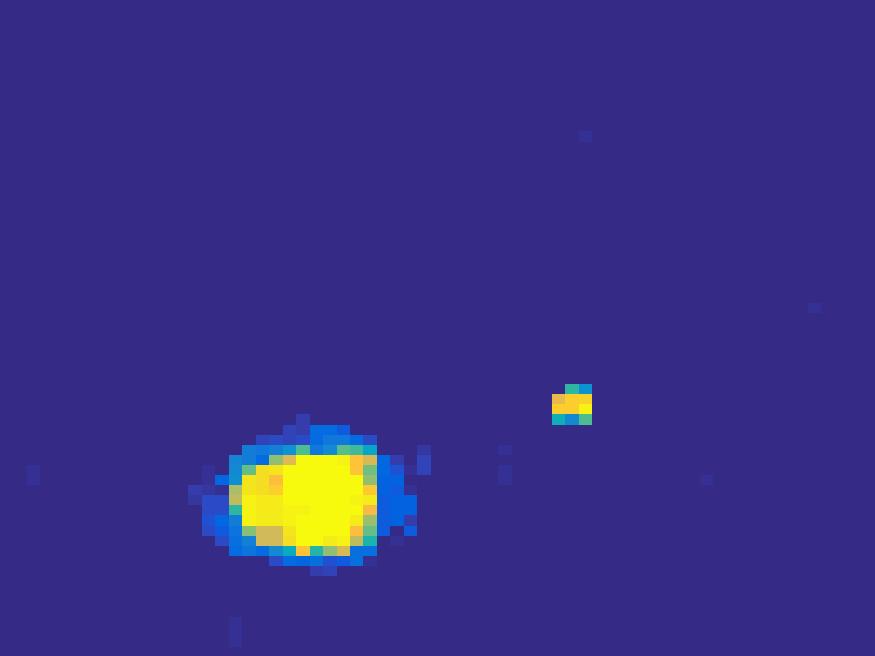

In order to test the performance of the proposed method in a more realistic scenario, we perform a Monte Carlo simulation for dynamic SPECT imaging. First, we created a phantom image consisting of three circles as region of interests, shown in Figure 13. The TAC over a time period of 90 time steps of the outer and the two inner circles were displayed in 13(b).

For each single frame, the photon counts is a probability proportional to the concentration in every region. The events are detected by a virtual double heads gamma camera rotating around the patient by degrees per time step, which consists of detector bins. Every simulated decay event is projected and counted by the corresponding detector bin.

We set the number of events counted by the detector as and ) times the average concentration in one pixel of two different tests. The signogram images the count in each bin of two settings are shown in Figure 14.

Based on the sinogram data, we compare the proposed method with the alternating EM algorithm. The results for both test cases are shown in Figure 15. We can see that for the case of a low count number, the proposed method is able to reconstruct the regions properly. Within a number of iterations, the algorithm presents a reasonable reconstruction of the region of interest and the corresponding regional tracer concentration curves.